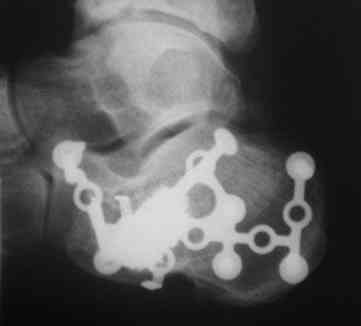

Точность репозиции суставной поверхности задней фасетки суставной поверхности пяточной кости на представленной вами рентгенограмме вызывает глубокие сомнения, так же как и конечный результат лечения в долгосрочной перспективе. По всей вероятности, у больного был перелом пяточной кости по классификации Sanders типа II A. Часть суставной поверхности задней фасетки, оставшаяся с sustentaculum пяточной кости (короткая линия на вложении, соответствующая субхондральному слоя репонированного фрагмента) находится на месте. А вот большая часть суставной поверхности так и осталась компримирована (длинная линия на вложении, соответствующая субхондральному слою компримированного фрагмента). При репозиции эти две линии должны совпадать. После репозиции, компримированный фрагмент следовало фиксировать к sustentaculum отдельным винтом (не всегда просто точно попасть). Пяточная пластина смещена к пяточному бугру, что не позволило фиксировать к ней самый проблемный участок пяточной кости – суставную поверхность. Не лишней здесь после репозиции была бы и костная пластика.

С уважением, VlaD.

calcaneus 3.jpg